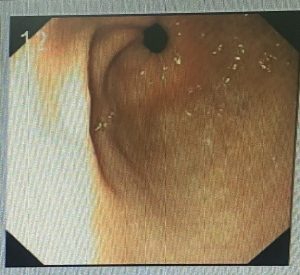

MỘT SỐ HÌNH ẢNH TRONG QUÁ TRÌNH ĐIỀU TRỊ BỆNH NHÂN

Hình 4. Đường kính stent giãn tối đa sau 2 tuần đặt